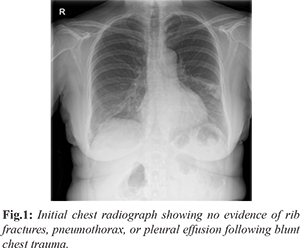

We report the case of a 64-year-old woman who sustained a fall, resulting in blunt trauma to the right side of the chest. She was initially evaluated at the Urgent Care Service, where clinical examination was unremarkable. Chest radiography demonstrated no evidence of rib fractures, pneumothorax, or pleural effusion [Fig.1]. The patient was discharged with analgesics and provided with safety-netting advice, including instructions to seek medical attention if her symptoms worsened.

Three days later, she presented again to the Emergency Department with increasing right-sided chest pain. Clinical examination remained unremarkable. However, repeat chest radiography revealed right lower zone consolidation with a mild pleural effusion [Fig.2]. Her prior history of trauma was not adequately considered, and she was referred to the Same Day Emergency Care (SDEC) unit. A provisional diagnosis of lower respiratory tract infection was made, and she was managed with oral antibiotics and analgesics, with advice for follow-up imaging. Subsequently, the patient reported with new-onset dyspnea and persistent right-sided chest pain. On examination, reduced air entry was noted on the right side. Repeat chest imaging demonstrated a progressive increase in the right-sided pleural effusion without evidence of pneumothorax [Fig.3]. A subsequent computed tomography (CT) scan of the chest identified multiple right-sided rib fractures along with a moderate pleural effusion, suggestive of an evolving haemothorax [Fig.4,5].

The patient was transferred to the resuscitation area, where an intercostal chest tube was inserted [Fig.6], yielding approximately 1000 mL of blood. Following cardiothoracic consultation, she was admitted under the surgical team for further management. Her clinical condition improved progressively [Fig.7,8], and the chest tube was removed after seven days. She was discharged in stable condition with planned follow-up in the surgical outpatient clinic.